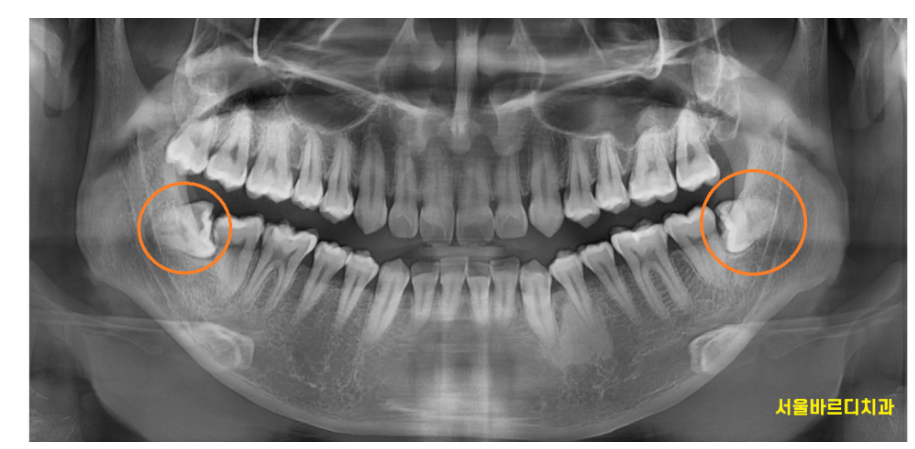

사랑니는 어금니 맨 뒤쪽에 나는 세 번째 어금니입니다.

아예 없는 사람도 있고,

잇몸 뼈 안에 묻혀 있는 경우도 많습니다.

230725 해당 환자분은 누워있고 묻혀있네요~~